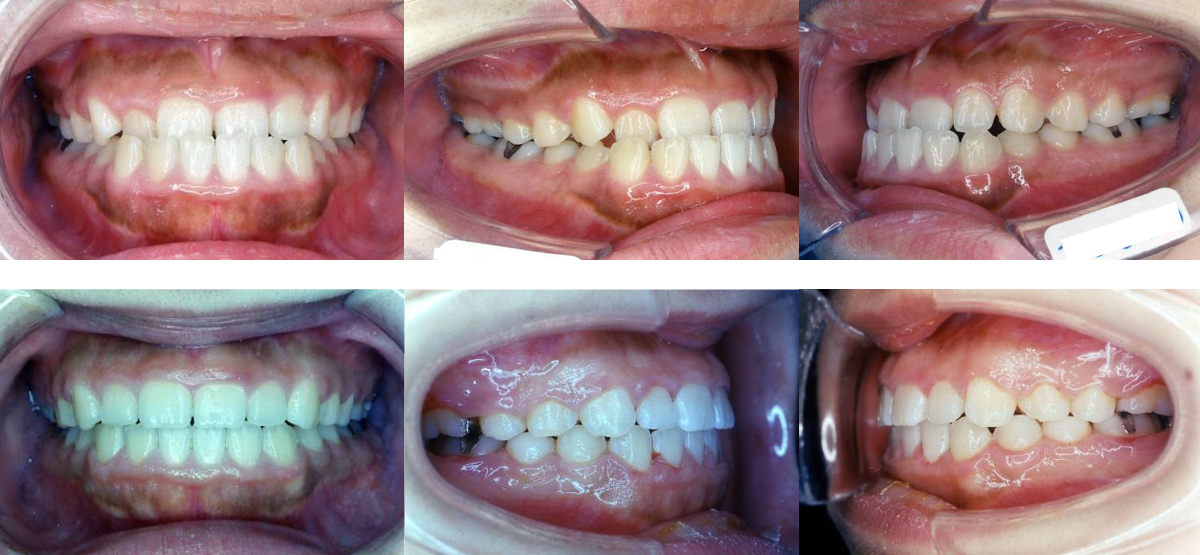

②受け口(下顎前突)の矯正治療例(20代男性・治療期間2年3か月)

| 年齢・性別 | 20代男性 |

| 治療期間 | 2年3か月 |

| 抜歯 | なし |

| 治療費 | 50万円(調整費、保定費まで含む総額制) |

| 備考 | インビザライン、インプラントで下顎遠心移動 |

| リスク・副作用 | 痛み・治療後の後戻り・歯根吸収・歯髄壊死・歯肉退縮 |

③受け口(下顎前突)の矯正治療例(10代女性・治療期間2年)

| 年齢・性別 | 10代女性 |

| 治療期間 | 2年 |

| 治療費 | 100万円(調整費、保定費まで含む総額制) |

| 備考 | 裏側矯正 |